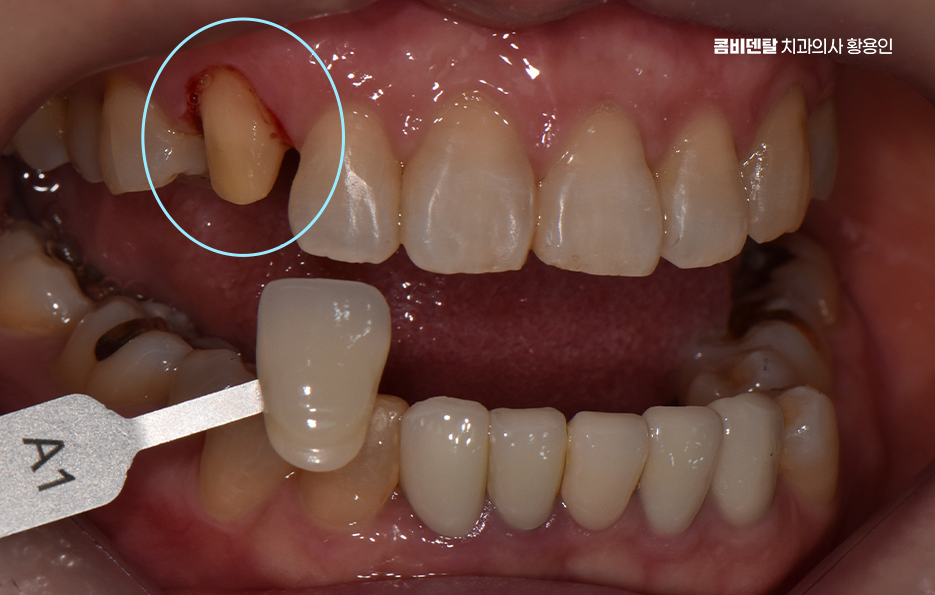

어릴 때는 송곳니가 나름의 포인트처럼 보였고, 웃을 때 조금 튀어나와 보이는 게 오히려 귀여운 느낌이라고 생각했을 만큼 별다른 불만도 없었고, 기능적으로도 별 신경 쓰지 않고 살았는데, 어느 날 그 송곳니에 작은 금이 간 걸 발견하면서부터 생각이 달라지게 됐어요, 처음에는 단순히 스치듯 지나가는 불편함이었고, 거울을 봐도 겉으로는 별다른 이상이 없었기에 그냥 피곤하거나 단단한 걸 씹다 살짝 충격을 받은 것뿐이겠지 하고 넘겼어요, 그런데 시간이 지나면서 그 송곳니 주변에 묘한 감각이 생기기 시작했고, 특히 찬물이나 단 음식이 닿을 때마다 찌릿한 시림이 점점 더 자주 찾아오면서 단순한 문제가 아니라는 걸 실감하게 됐어요. 정확히 언제, 어떤 이유로 그렇게 손상이 된 건지는 알 수 없었지만, 분명한 건 그동안 송곳니가 많은 역할을 해왔다는 거였어요, 다른 치아에 비해 뿌리도 깊고, 입꼬리 쪽에서 중요한 균형을 잡아주는 역할을 하다 보니 교합이나 저작 시에도 무게를 많이 견디는 위치인데, 그만큼 미세한 손상이 쌓이면 결국 파절이나 크랙으로 이어질 수 있다는 걸 나중에야 알게 됐어요, 다만 이미 치질이 약해진 상태라서 송곳니 크라운을 해야 했는데 송곳니는 눈에 잘 띄는 치아 중 하나인데, 거기를 깎고 덮는다는 게 쉽게 받아들여지진 않았고, 뭔가 내 얼굴 전체 인상이 바뀌는 건 아닐까 하는 걱정도 들었어요.

이처럼 송곳니의 손상은 비교적 눈에 잘 띄는 부위에 속하기 때문에 앞니 만큼이나 심미적인 치료가 중요한 부위이기 때문에 크라운 치료를 해야 한다면 심미성과 기능을 함께 고려한 치료가 중요할 수 있는데요

특히 송곳니 크라운 치료가 필요한 상황이라면, 단순히 기능 회복만 생각할 게 아니라 모양과 색감까지 자연스럽게 복원하는 게 중요하겠고 이런 경우에 적합한 방법이 바로 올세라믹이나 지르코니아 크라운을 이용한 심미적인 치료라고 할 수 있어요

크라운 치료는 치아가 많이 손상됐을 때, 또는 신경치료 후 치아가 약해졌을 때 치아를 보호하고 형태를 회복시키기 위한 보철 치료인데 쉽게 말하면 보통 씌우기 치료라고 말하는 치아를 보철물로 전체를 덮는 치료로 송곳니처럼 앞쪽에 위치한 치아는 씌운 게 티 나지 않게 만들어야 하니까 재료 선택이 중요하다는 점에서도 올세라믹과 지르코니아 같은 재료가 주로 활용되고 있었어요

올세라믹 크라운은 말 그대로 금속이 전혀 들어가지 않은 세라믹 재료로 만들어진 크라운으로 금속 없이 순수한 도자기로만 제작되기 때문에 빛 투과성이 자연치아와 거의 비슷하고, 치아 본연의 반투명한 느낌을 재현할 수 있으며 특히 송곳니처럼 햇빛이나 형광등 아래에서 드러나기 쉬운 치아는 빛에 반응하는 느낌이 중요한데 올세라믹은 이런 부분에서 우수한 심미성을 보여주는 재료로 말할 때나 웃을 때 자연스럽게 어우러져서 보철물이 있다는 걸 거의 눈치챌 수 없게 만들어줄 수 있을 정도로 송곳니 크라운 재료에서 심미적인 장점이 있어요